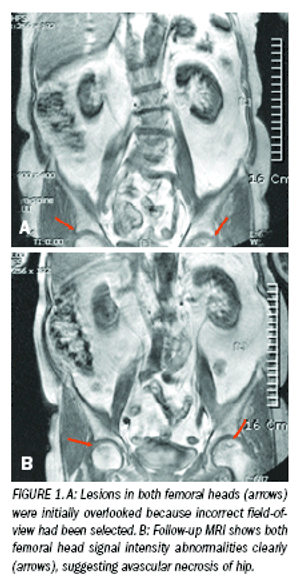

Critical hip disorders show upon spinal imaging studiesByHyung Seok Kim, MDJuly 1st 2009When patients are suffering from back pain and radiating pain in their lower extremities, it is usual to suspect that the symptoms are caused by a spinal disorder.